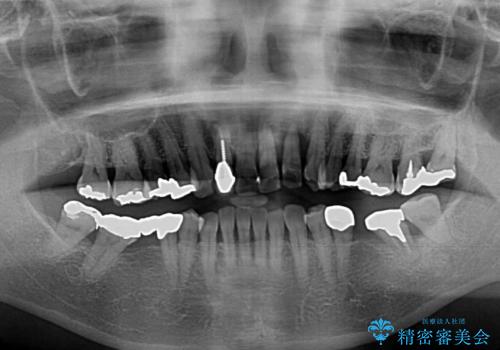

- 前歯の歯肉の腫れを気にして来院された患者様です。

前歯のみならず、奥歯の銀歯や下顎前歯のデコボコなど、色々と気になる部分を治したいとのことでした。

前歯は抜歯が必要であったので、抜歯を行い、その後歯肉移植をおこなった上でオールセラミックブリッジによる補綴治療を行うこととしました。

下顎と上顎臼歯部については矯正治療を行い、奥歯の欠損部位はオールセラミックブリッジを、その他の銀歯はセラミックインレーなどにより治療を行うこととしました。